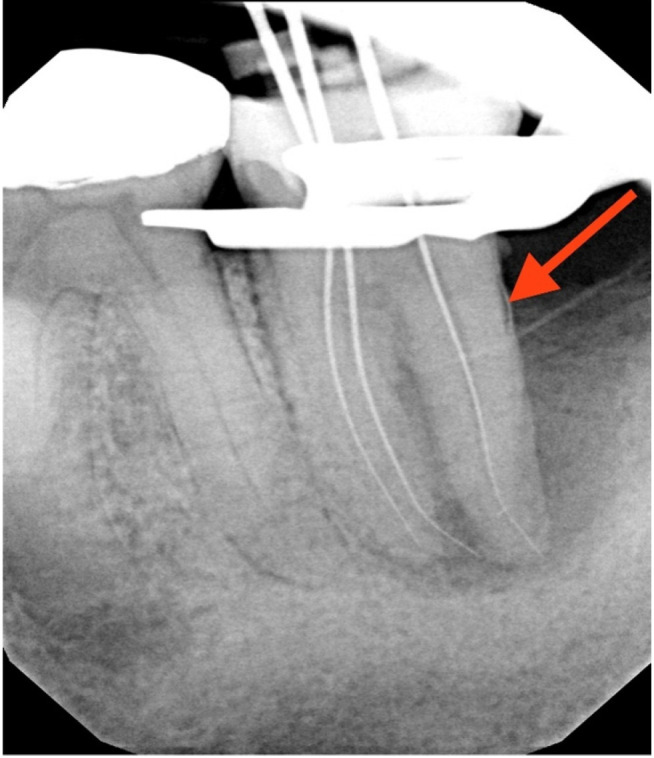

牙髓-牙周病变并发牙髓撕裂是一个诊断和治疗上的挑战。本病例报告描述了一位66岁男性下颌第二磨牙患者(#18)的成功治疗,该患者表现为EPL合并骨水泥撕裂。临床检查显示窦道引流,牙周深袋,x线表现为“j形”病变和不透射线的骨水泥碎片。该牙齿曾接受过牙髓治疗。多学科的方法包括牙髓治疗和手术切除骨水泥撕裂。在24个月的随访中,临床和影像学检查显示牙周健康、骨再生和病变消退有显著改善。本病例强调了在鉴别诊断epl时考虑骨水泥撕裂的重要性,并证明了牙髓-牙周联合入路对实现可预测结果的有效性。

Endodontic-periodontal lesions (EPLs) complicated by cemental tears present a diagnostic and therapeutic challenge. This case report describes the successful management of a 66-year-old male patient with a mandibular second molar (#18) exhibiting an EPL complicated by a cemental tear. Clinical examination revealed a draining sinus tract, deep periodontal pockets, and radiographic evidence of a "J-shaped" lesion and a radiopaque cemental fragment. The tooth had previously initiated endodontic treatment. A multidisciplinary approach involving endodontic treatment and surgical removal of the cemental tear was implemented. At 24-month follow-up, clinical and radiographic examination revealed significant improvement in periodontal health, bone regeneration, and resolution of the lesion. This case highlights the importance of considering cemental tears in the differential diagnosis of EPLs and demonstrates the efficacy of a combined endodontic-periodontal approach for achieving predictable outcomes.